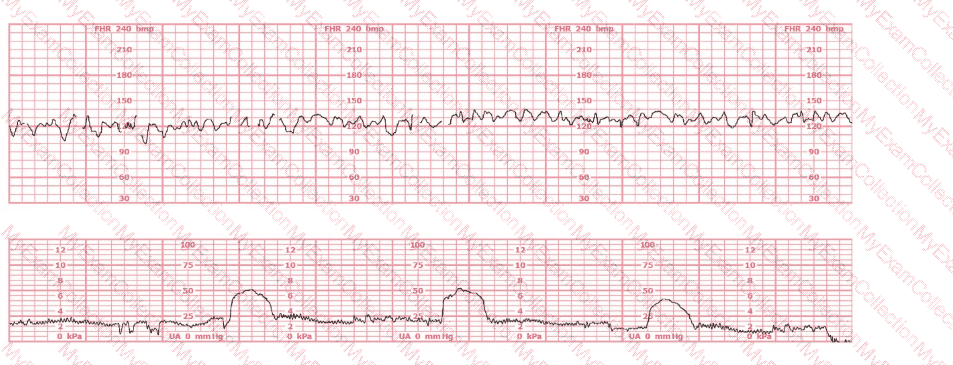

A woman has been 5 cm dilated for the past 3 hours. The tracing shown has developed over the last 30 minutes. The best initial course of action is to: